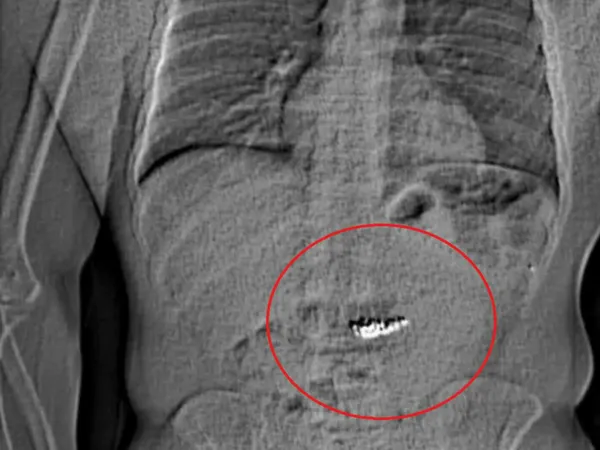

Poliția a publicat ulterior o radiografie care arată un obiect străin în abdomenul unui individ. Întrebați de BBC, reprezentanții Poliției din Orlando nu au precizat dacă bijuteriile au fost recuperate.